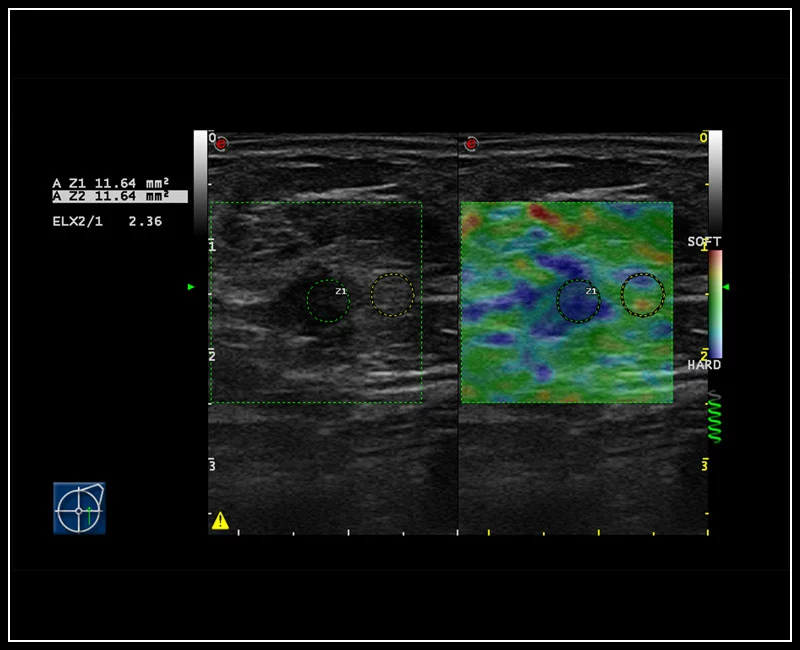

MyLab™9 Platform - Dual ElaXto characterization on breast lesion

MyLab™9 Platform - Dual ElaXto characterization on breast lesion